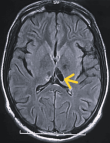

Diagnostic assessment: magnetic resonance imaging of the brain demonstrated an infiltrative thalamo-peduncular lesion with hyperintensity on T2/FLAIR sequences and faint enhancement on post-contrast T1, raising concern for an infiltrative high-grade glioma and creating diagnostic uncertainty (Figure 1, Figure 2). A stereotactic biopsy was subsequently performed. Initial histological evaluation suggested a high-grade glioma; however, immunohistochemical staining revealed strong positivity for CD117, PLAP, and OCT4, findings consistent with a pure germinoma (Figure 3, Figure 4). Staging with thoraco-abdominopelvic CT identified nonspecific pulmonary micronodules (Figure 5), while serum tumor markers remained within normal limits (Table 1). As shown above, the patient's LDH level is elevated compared to the reference range, while both β-HCG and α-FP are within normal limits. These values are important for the diagnostic evaluation and ongoing management of intracranial germ cell tumors.

Figure 1: contrast-enhanced brain magnetic resonance image showing a thalamo-peduncular lesion: axial T1-weighted post-contrast magnetic resonance image demonstrating a thalamo-peduncular mass with heterogeneous patchy enhancement and multiple small cystic components (red arrow)

Figure 2: axial T2-weighted brain magnetic resonance image showing a thalamo-peduncular mass: axial T2-weighted magnetic resonance image demonstrating a hyperintense lesion in the thalamo-peduncular region with surrounding edema and compression of the third ventricle